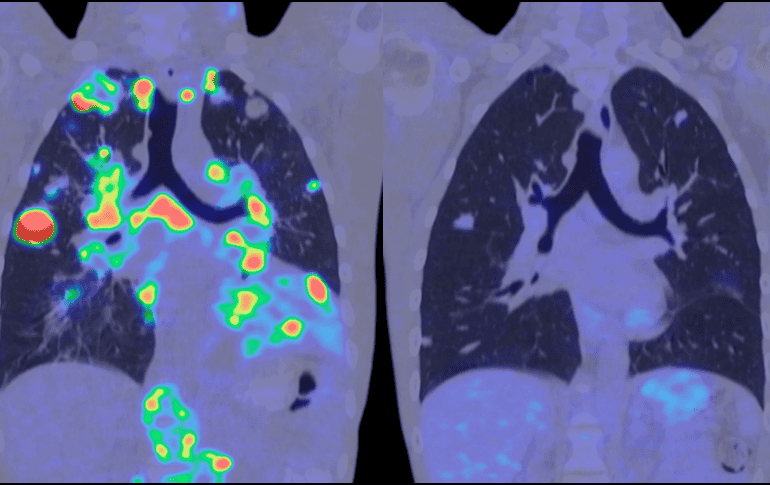

Entre los participantes había pacientes con cáncer de hígado, pulmón, ovario y estómago; con enfermedades hepáticas como la hepatitis B, la hepatitis C, con patología hepática relacionada con el alcohol y trastornos metabólicos; personas con nódulos pulmonares benignos; y participantes sanos.

En cuanto a la detección de múltiples tipos de cáncer, la prueba alcanzó un alto nivel de precisión general. Con una especificidad del 98%, lo que significa pocos falsos positivos, detectó alrededor del 63 % de los cánceres en todas las etapas y aproximadamente el 55% de los cánceres en fase inicial.

Más allá de la simple detección del cáncer, los patrones de metilación ayudaron a identificar de qué parte del cuerpo procedía una señal, lo que se conoce como tejido de origen.

Los autores señalan que MethylScan "puede funcionar como un radar de salud para el cuerpo". Al leer las señales de ADN en la sangre, puede determinar cuándo órganos específicos, como el hígado o los pulmones, están sometidos a estrés o dañados, incluso sin conocer la enfermedad de antemano.